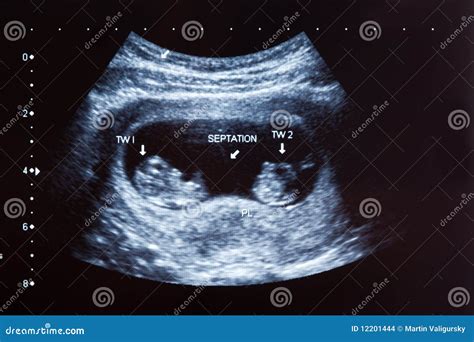

• Multiple Pregnancy Detection: If you are carrying twins or multiples, the 10 week sonogram can detect this early on.

At 10 weeks, the fetus is about the size of a strawberry, measuring approximately 1.2 to 2.5 inches in length. The 10 week sonogram can reveal several key features:

• Basic Structures: The ultrasound can show the early development of the brain, spinal cord, and other vital organs. The limbs, tail, and yolk sac may also be visible.